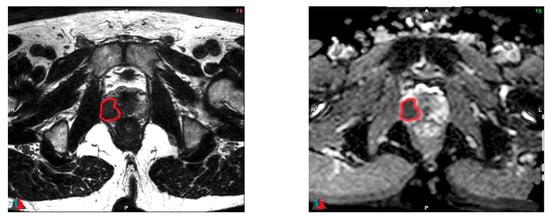

2.6. Tumor Delineation